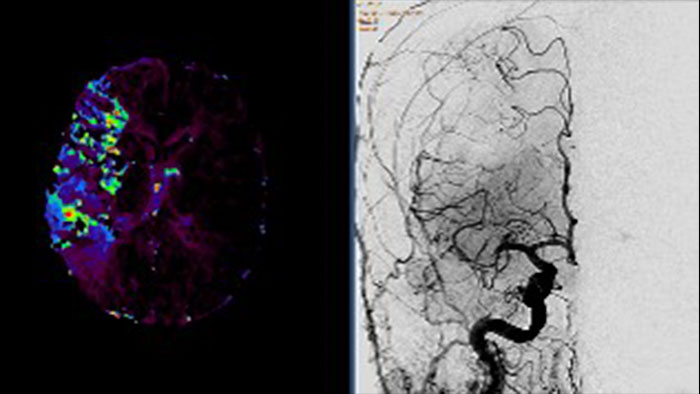

Dynamic Myocardial Perfusion (DMP)

CT Dynamic Myocardial Perfusion (DMP)

Dynamic color maps provide an assessment of myocardial risk

Provides automatic and manual tools to help visualize and assess signal intensity differences (in Hounsfield Unit) focusing on the left ventricular myocardium, providing quantitative myocardial perfusion measurements for CT images.

Benefits

• Supports axial, ECG-gated CTA images, consisting of multiple time shots within the same acquisition of the myocardial region over time (i.e. dynamic CT scans), after an injection of intravenous contrast.

• Automatic and manual tools providing quantitative myocardial perfusion parameters such as: Peak Enhancement, Time To Peak, Perfusion and Blood Volume, and provides color maps representation of the results and graphical representation of intensity curves.